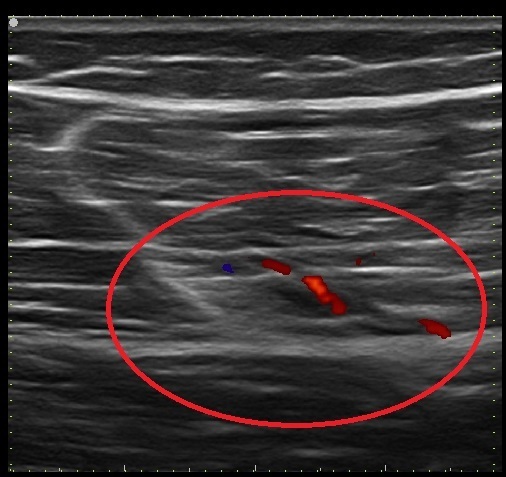

14歳 女性 左臀部肉離れ 症例1

筋膜と筋組織に低エコーにて確認

1週間前より左腰部に痛みあり、競技を続けるも痛み増悪し、当院来院。

エコー観察にて左大臀筋・中臀筋の筋膜損傷・中殿筋肉離れと判断。

また、血流反応も確認。